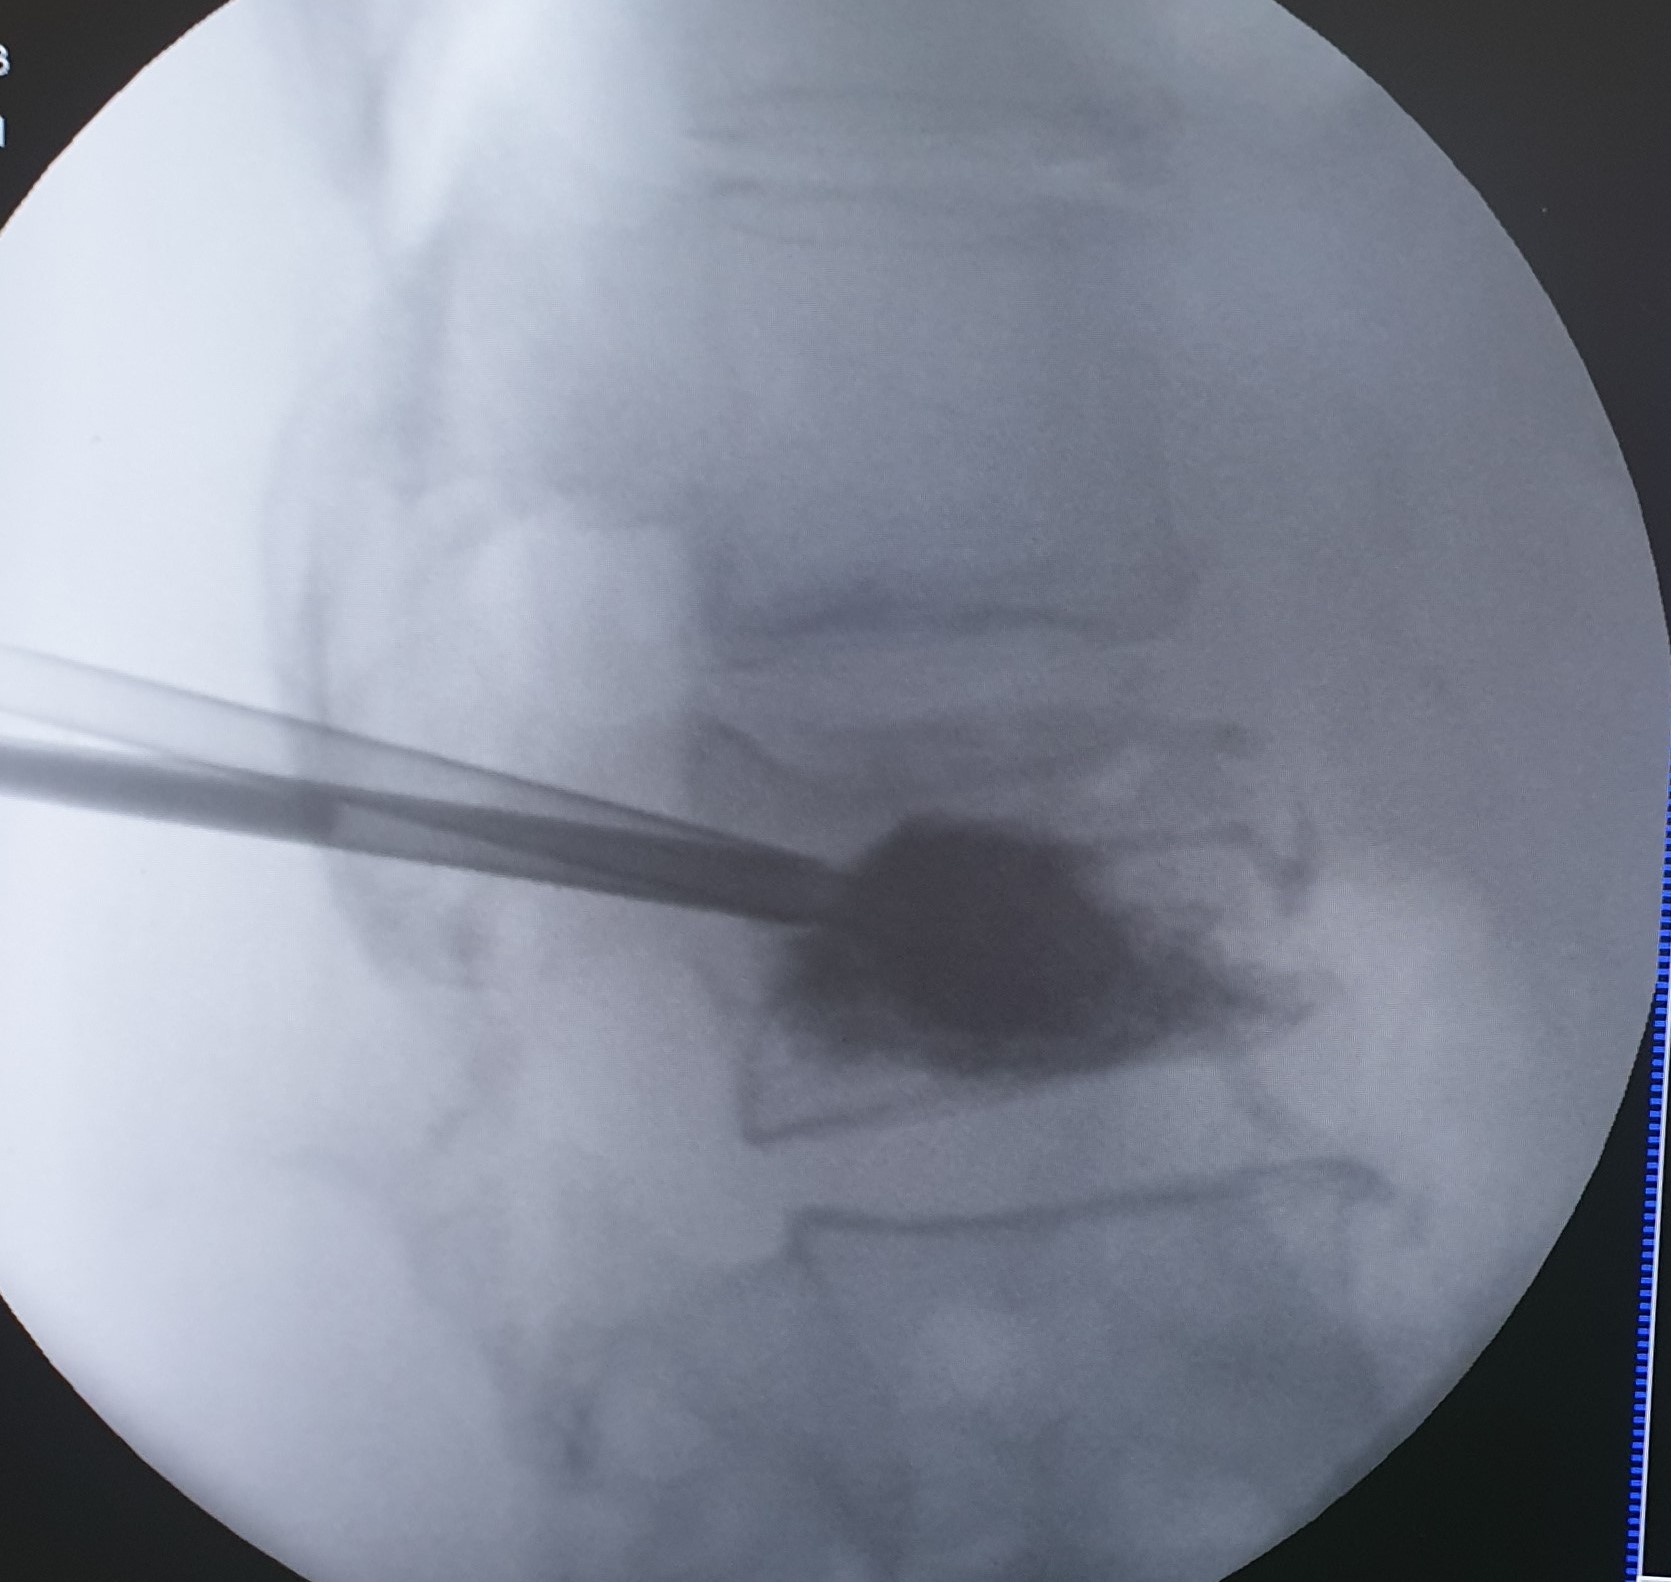

Η κυφοπλαστική και η σπονδυλοπλαστική αποτελούν ελάχιστα επεμβατικές τεχνικές αντιμετώπισης του πόνου που προκαλείται από συμπιεστικά καταγμάτα των σπονδύλων, επί εδάφους οστεοπόρωσης ή μεταστατικής νόσου. H προσπέλαση και στις δύο περιπτώσεις γίνεται διαδερμικά και κάτω από συνεχή ακτινοσκοπική καθοδήγηση.

Η κυφοπλαστική αποκαθιστά το ύψος του σπονδύλου, με χρήση ειδικού μπαλονιού και εισαγωγή τσιμέντου, ενώ η σπονδυλοπλαστική αφορά σε απλή εισαγωγή τσιμέντου στον καταγματικό σπόνδυλο. Και οι δύο τεχνικές γίνονται μέσω ειδικών βελόνων-trocar που εισάγονται διαδερμικά υπό ακτινοσκοπικό έλεγχο, στους αυχένες των σπονδύλων και προωθούνται στο σπονδυλικό σώμα, όπου γίνεται η έγχυση του τσιμέντου ταχείας πήξης. Το τσιμέντο σταθεροποιεί τον σπόνδυλο και αποτρέπει την ανάπτυξη κύφωσης στα πάσχοντα σημεία.